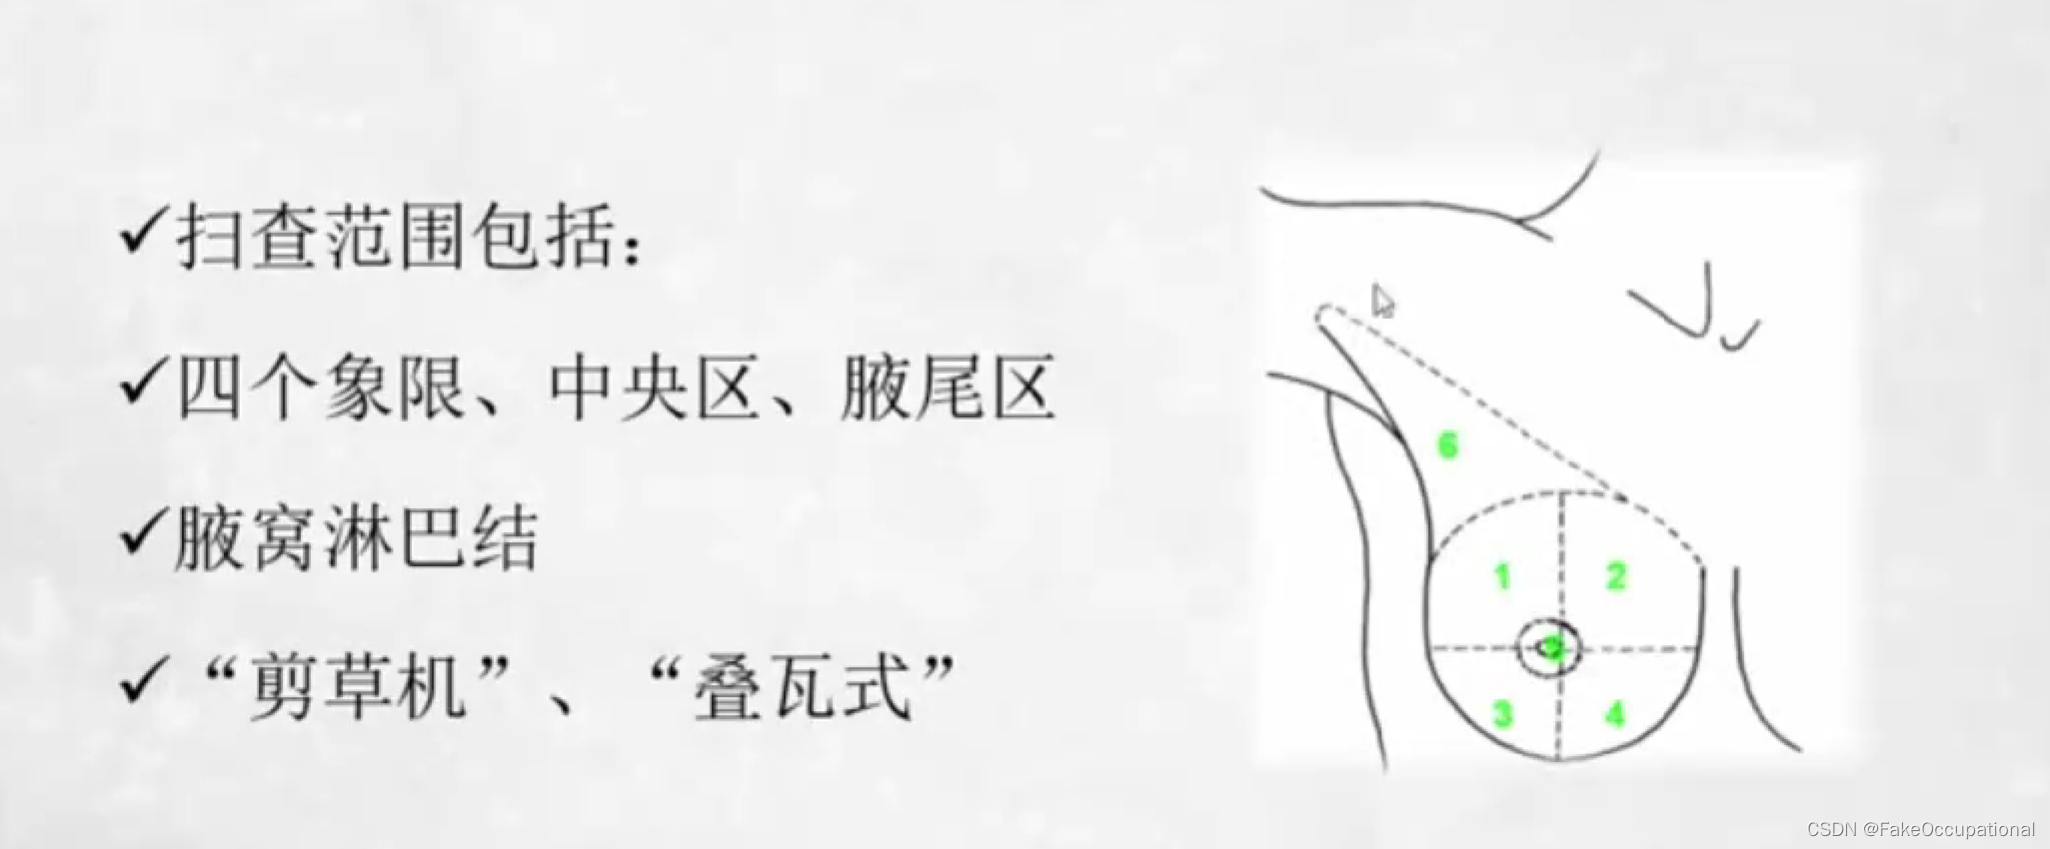

乳腺超声检查技术

- 检查前患者无特殊准备,对月经周期并无太大要求

乳腺检查注意事项

- 双侧对比:检查时先健侧、后患侧

- 避免加压: 探头轻放,以免改变肿块形态、位置或影响肿块内血流显示,必要时加压

- 全面扫查: 乳头后区域适当斜切,必要时可增加耦合剂